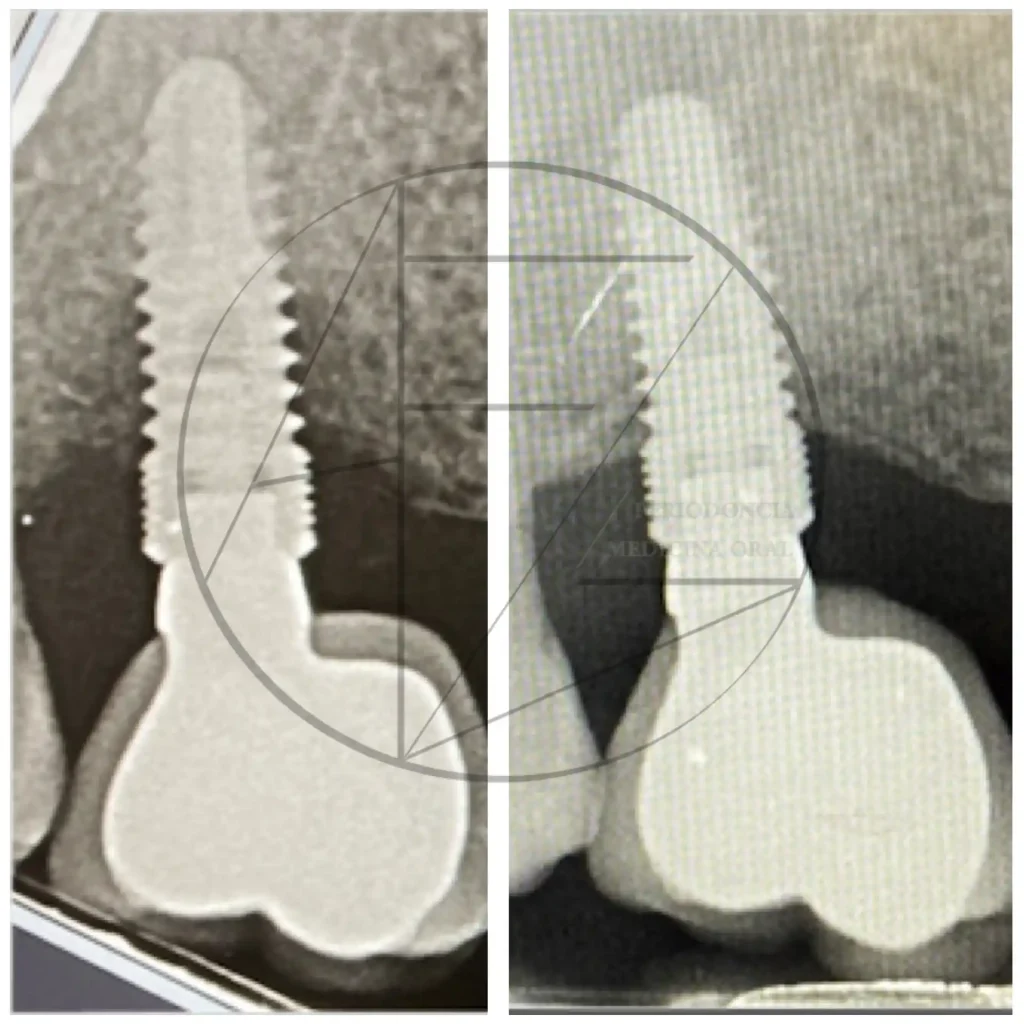

Periimplantitis